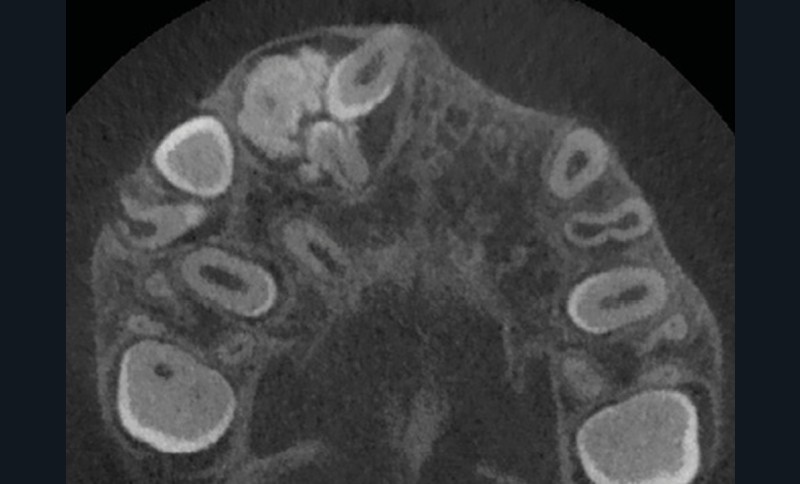

La radiographie panoramique permet une première interprétation de la lésion osseuse (localisation, nombre, taille approximative, etc.). Cet examen est souvent complété par un bilan d’imagerie en trois dimensions de type Cone Beam [4]. Il précisera le volume et les limites de la lésion ainsi que ses rapports avec les structures anatomiques avoisinantes (tableau 1). Ces données radiologiques confrontées à l’examen clinique et à la fréquence relative des lésions permettent de réaliser un diagnostic d’intuition qui orientera la prise en charge.